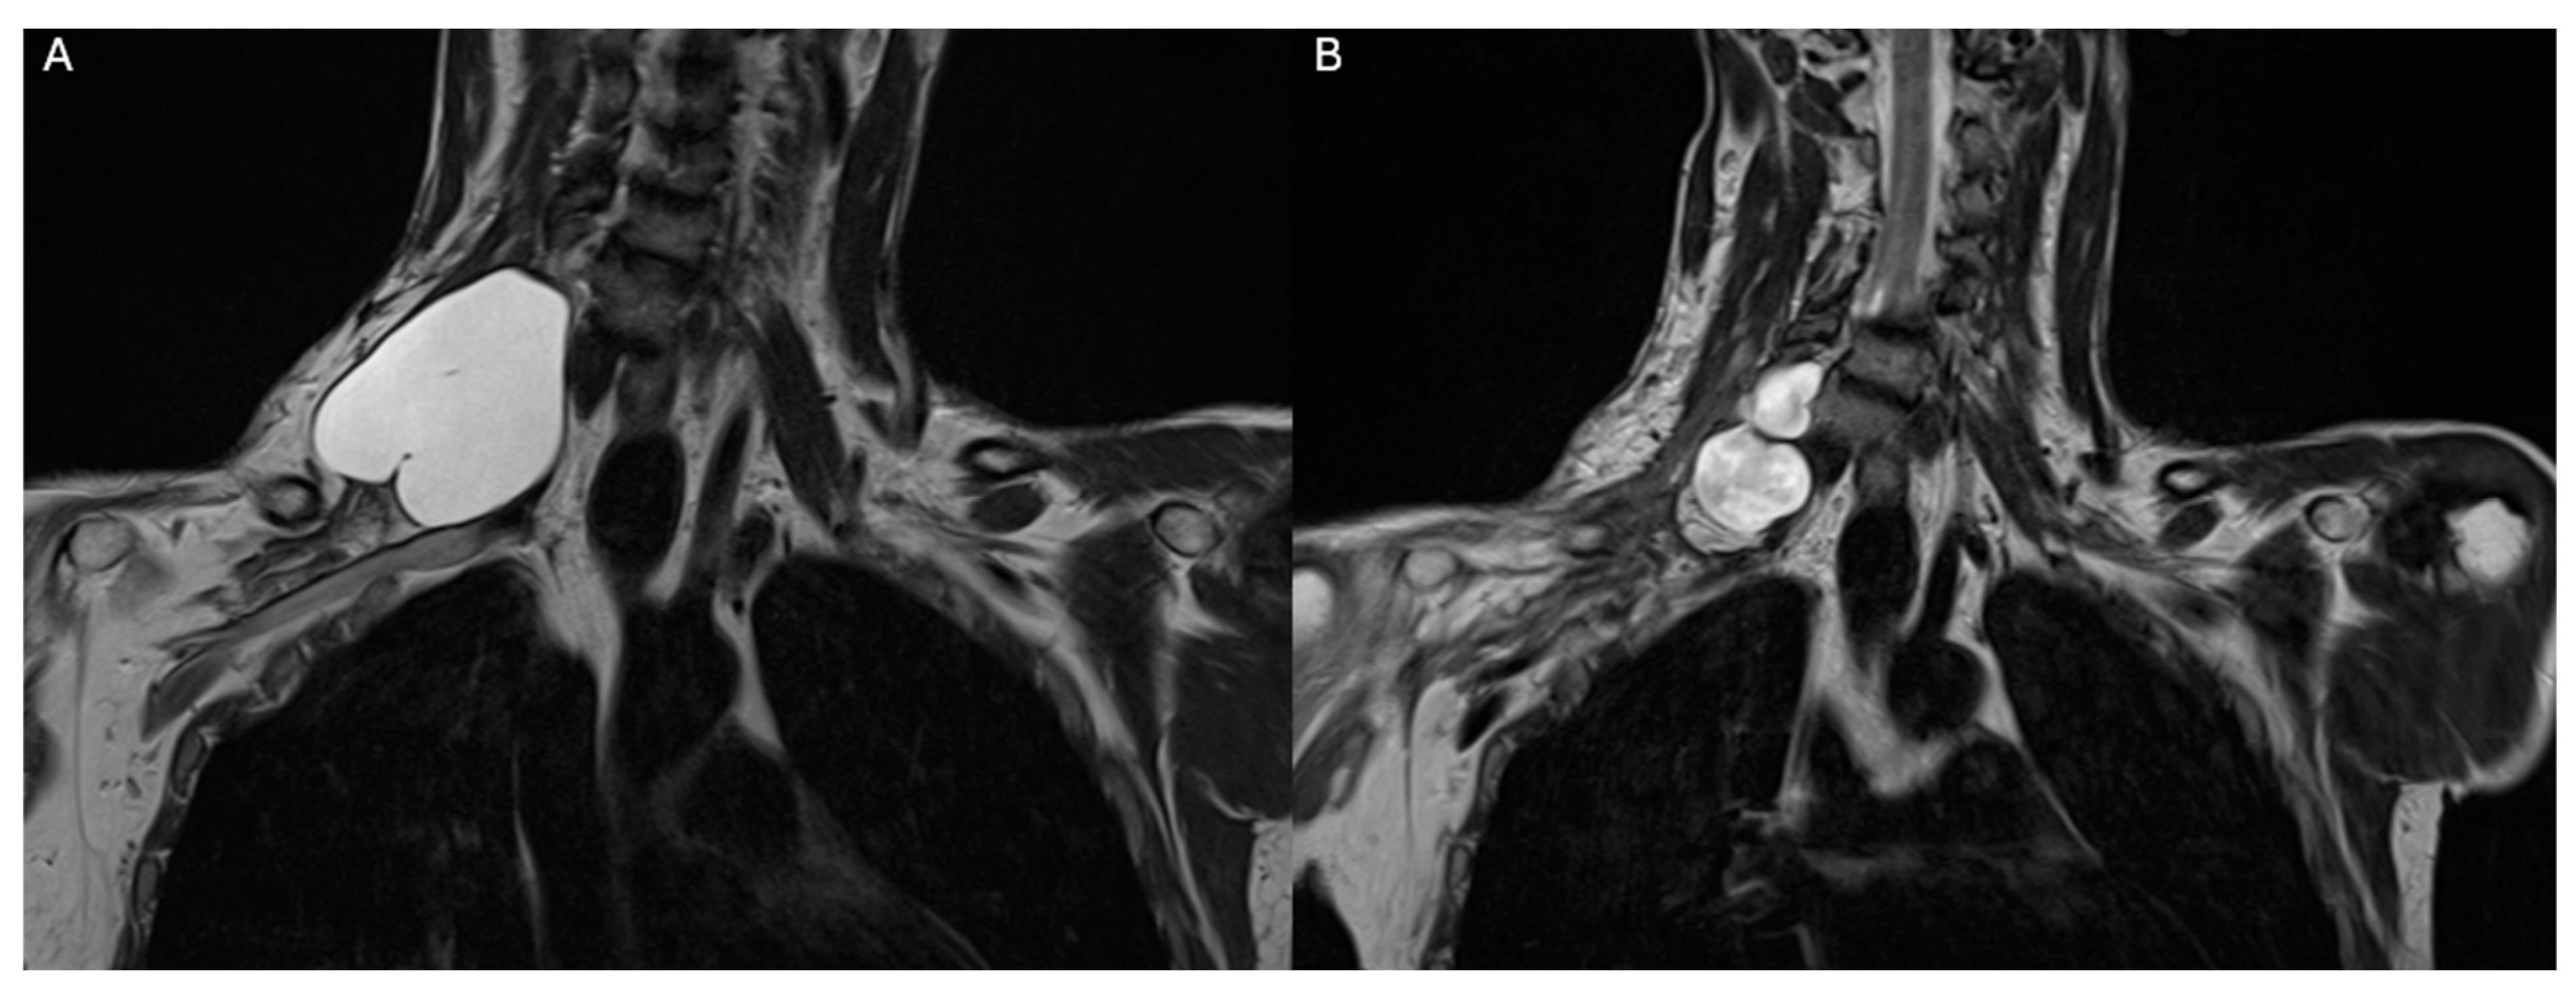

3. Case Report